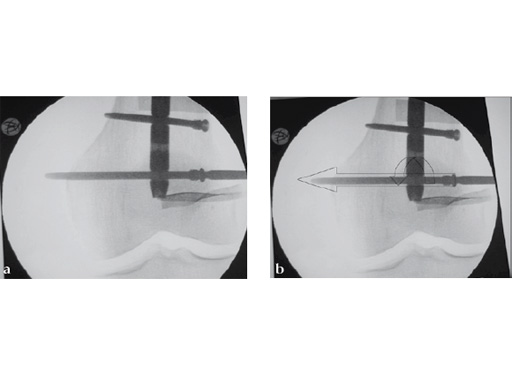

Drilling is identical but the near cortex needs additional reaming so it is wide enough to insert the sleeve. The enlarged hole at the near cortex will be filled by the thicker part which has a larger diameter than the rest of the screw (Fig 2). Use of the hand reamer has proven to be more tactile compared to drilling with machines (Fig 3). Power-driven drilling is only needed for very strong cortices, eg, the femur.

The screw-sleeve construct is pushed into the nail's locking hole by hand. For the final placement, a light hammer (100 gr) may be used (Fig 8). You can actually feel and even hear the correct positioning. Use of a heavier hammer may lead to too deep placement or even pushing the sleeve too far through the locking hole. Control by image intensifier of the reamer and/or screw placement is only needed in the very early part of the learning curve (Fig 9).